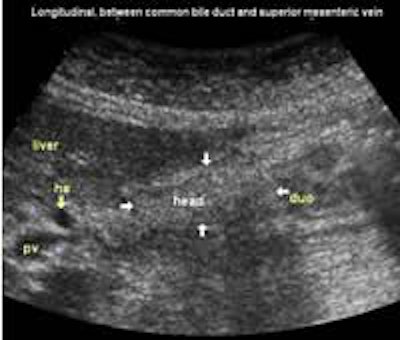

The following study describes anatomical landmarks in the ordinary pancreas of a thin patient:

Transverse planes in caudal direction: